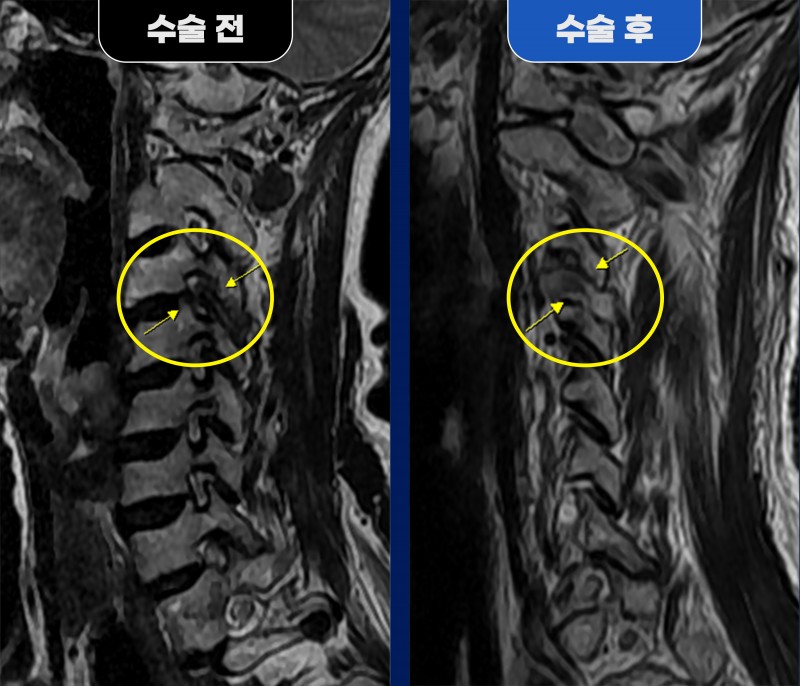

■ Before (수술 전) 68세 여성 환자분께서 갑작스러운 좌측 뒷머리 통증과 어지럼증으로 휠체어를 타고 내원하셨습니다. 왼쪽 어깨·승모근·등(날개뼈 주변) 부위에도 극심한 통증이 동반되어 뇌혈관 질환(뇌출혈·뇌경색) 가능성을 의심했으나, MRI·MRA 검사상 특이소견은 없었습니다. 추가로 시행한 경추 검사 결과, 오랜 일자목으로 인해 경추 근육이 단단히 뭉쳐 있고, 경추 3~4번 부위에서 퇴행성 변화(관절염, 석회화, 전방 전위) 가 진행되며 신경을 심하게 압박하고 있는 추간공 협착증이 확인되었습니다. 이로 인해 후두부부터 어깨·등까지 이어지는 신경통과 근막통증이 발생한 상태였습니다. 약물치료와 신경차단술에도 통증이 하루밖에 완화되지 않아, 수술적 치료가 불가피한 상황이었습니다. ■ After (수술 후) 환자분은 단일공 내시경을 통한 경추 3/4번 추간공 감압술을 받으셨습니다. 수술 중, 자라난 뼈조직(골극), 석회화된 관절막, 두꺼워진 인대 등이 신경을 압박하고 있는 것이 확인되었으며, 이를 모두 제거하여 신경의 통로를 확보했습니다. 수술 후 MRI에서 눌렸던 신경이 정상적으로 복원된 모습이 관찰되었고, 환자분은 즉시 통증과 어지럼 증상이 호전되어 3일 만에 퇴원하셨습니다. 청담해리슨송도병원은 단순히 통증 부위를 치료하는 데 그치지 않고, 신경 압박의 원인을 정밀하게 진단하고 맞춤형 내시경 수술로 근본 원인을 해결합니다. 목 뒤·어깨 통증이 반복되거나, 원인 모를 두통과 어지럼이 지속된다면 경추 협착증이나 신경 압박이 원인일 수 있습니다. 정확한 진단과 조기 치료가 회복의 핵심입니다. |